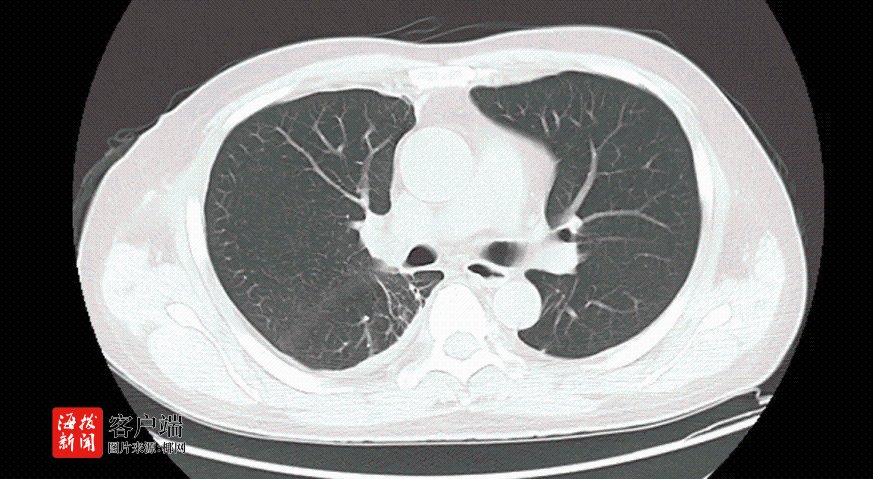

据了解,卢先生因车祸被120紧急送入该院救治。入院时,医护人员迅速检查发现,他不仅右侧液气胸(少量)、创伤性湿肺、椎体压缩性骨折,还出现了面色苍白、心率加快、血压下降,血色素急剧下降等症状。胸部CT检查更是显示,他的右侧胸腔大量积血,肺压缩高达80%,右胸腔大片高密度影较前增大,生命岌岌可危。

面对如此危急的病情,医护人员在急诊床旁为卢先生行右侧胸腔闭式引流术,胸腔引流管引出大量暗红色血性液体。该院胸外科副主任刘运仲也迅速赶到现场会诊。他凭借丰富的急救经验,果断判断卢先生胸外伤未合并肋骨骨折,但有大量气胸,肺部破裂,右胸腔大片高密度影及胸腔引流出的大量血性液体均提示有胸腔大出血的情况,但大出血原因不明。考虑到卢先生发病突然,且疾病进展快,凶险程度高,时间紧迫,他立即向胸外科主任赵宏光汇报,并准备进行手术探查止血。